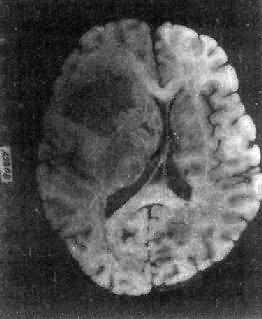

图16-23 星形胶质细胞

左大脑半球肿胀,肿边界不清,部分呈胶冻状

高度恶性的星形胶质细胞称为多形性胶质母细胞(glioblastoma multiforme),多见于成人。肿好发于额叶、颞叶白质,浸润范围广,常可穿过胼胝体到对侧,呈蝴蝶状生长(图16-24)。体因常有出血坏死而呈红褐色。镜下,细胞密集,异型性明显,可见怪异的单核或多核巨细胞。出血坏死明显,是其区别于间变性星形胶质细胞的特征。毛细血管明显增生,内皮细胞增生、肿大,可导致管腔闭塞和血栓形成。肿发展迅速,预后极差,患者多在2年内死亡。

在两半球内肿呈蝴蝶状,边界不清,切面见有出血、坏死及液化